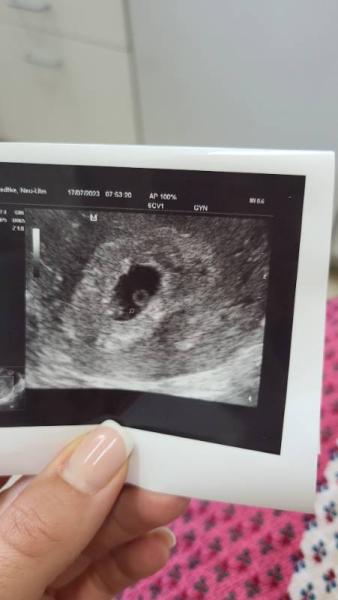

Hi ihr Lieben, würde gerne wissen ob ihr nach der Ramzi Methode erkennen oder schätzen könnt was es wird. Das Bild entstand durch vaginalen Ultraschall in der 7ten Woche.

Bild zu Junge oder Mädchen - Baby Forum - Allgemeine Themen